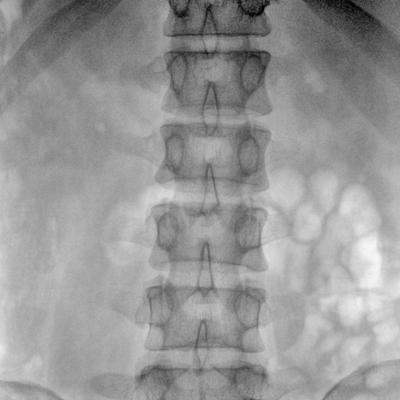

大尺寸動態(tài)平板探測器,高DQE、低噪聲、圖像清晰。采用多分辨率圖像增強處理技術(shù),不同部位不同圖像處理算法,滿足客戶多樣化的需求。